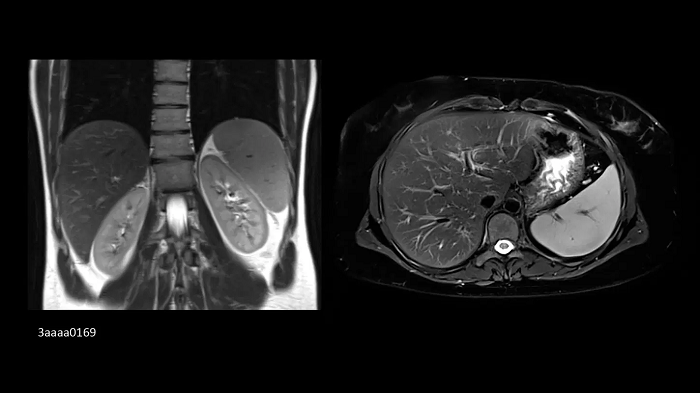

Orthopedics

Hip imaging with the new Ultraflex Coils

In pediatrics, high-resolution bilateral hip imaging with the new UltraFlex Coils was performed on an 8-year-old boy.

Image Credit: Radiologie Miinchen Harlaching, Munich, Germany